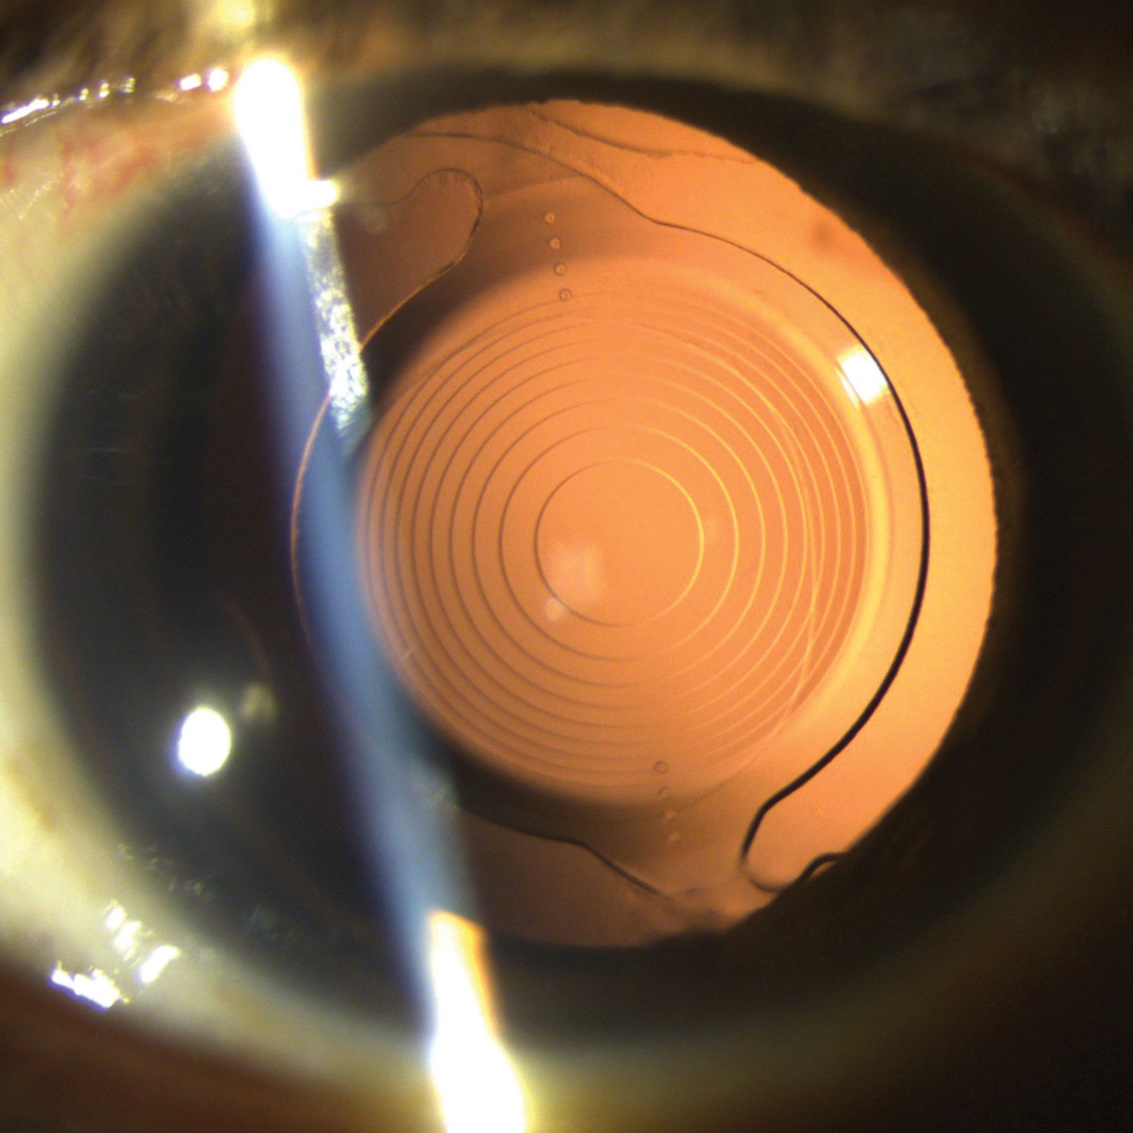

This roundtable is a follow-up discussion from the 2021 Satellite Program, "Nailing Your Toric Outcomes." This session will include dynamic faculty and various case studies on key factors for achieving your toric outcomes, formulas and alignment methods and addressing ways to select Toric IOLS for post-refractive eyes.